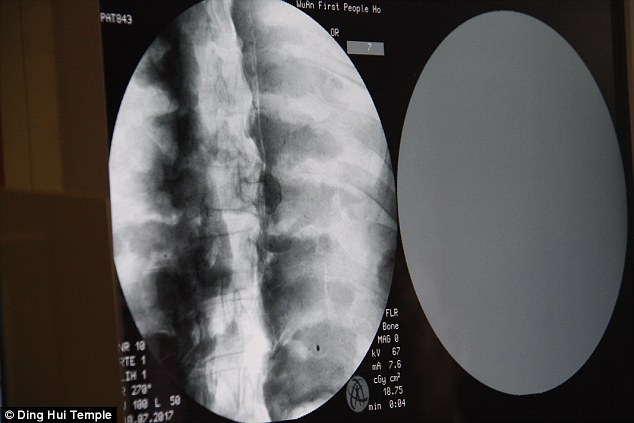

Sự kiện gây chấn động diễn ra vào ngày 8 tháng 7 năm 2017, khi các nhà khoa học tiến hành chụp CT để kiểm tra bên trong "bức tượng" này trước sự chứng kiến của giới truyền thông và đông đảo người dân. Kết quả hình ảnh quét được đã khiến tất cả những người có mặt phải bàng hoàng. Các bác sĩ xác nhận rằng bên dưới lớp mạ vàng, nhà sư Ci Xian vẫn giữ được bộ xương nguyên vẹn cùng một bộ não hoàn chỉnh.

Kết quả hình ảnh từ máy quét đã khiến toàn bộ giới khoa học và những người chứng kiến phải kinh ngạc đến mức sững sờ. Các bác sĩ xác nhận rằng nhà sư Ci Xian vẫn còn giữ được một bộ xương hoàn chỉnh cùng một bộ não nguyên vẹn.

Bác sĩ Wu Yongqing, người trực tiếp tham gia buổi kiểm tra cho biết xương của ngài khỏe mạnh và rõ ràng như một người bình thường. Từ xương hàm trên, răng, xương sườn, xương sống cho đến tất cả các khớp đều vẫn còn nguyên vẹn một cách khó tin. Sự tồn tại hoàn hảo của thi hài sau hơn 1.000 năm đã chứng minh kỹ thuật ướp xác đỉnh cao thời bấy giờ, tạo nên một hiện tượng chấn động khiến cả thế giới phải chú ý.